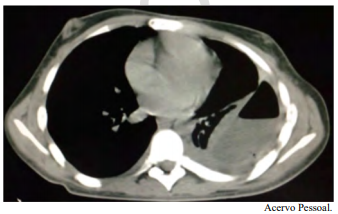

Um paciente do sexo masculino, jovem de 21 anos de idade, com diagnóstico prévio de esquizofrenia, foi internado para investigação de alteração na tomografia de tórax, conforme a imagem a seguir. A clínica apresentada era perda de peso, febre vespertina, tosse e um episódio de hemoptise. É familiar contactante de paciente com tuberculose ativa.

Com base nesse caso clínico e nos conhecimentos médicos correlatos, julgue o item a seguir.

Pleurodese está indicado como tratamento definitivo desse caso.